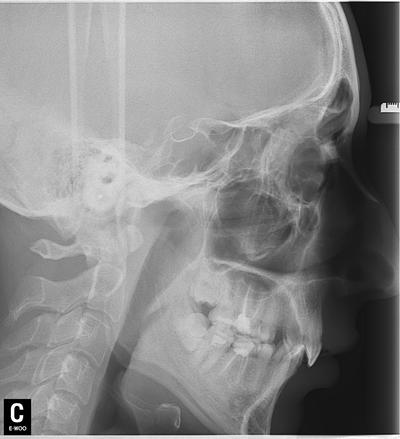

Вам сказали фигню! Вот снимок этой пациентки до лечения.

Как стоматолог, поясняю - здесь проводится ортодонтическое лечение. Явно не просто так, у пациентки были проблемы прикуса, которые привели к снижению межальвеолярной высоты. Это означает, что нижняя челюсть вывернута вверх и кпереди от своего нормального положения, что приводит к перенепряжению групп мышц вплоть до нарушения кровоснабжения головы и шеи. Кто не видит логики - постоянный гипертонус мышц пережимает сосуды. Попробуйте выдвинуть нижнюю челюсть вперед и кверху - через несколько минут заболит голова. При снижении высоты прикуса это становится хроническим, организм начинает рефлекторно сбрасывать это напряжение задействуя другие группы мышц.